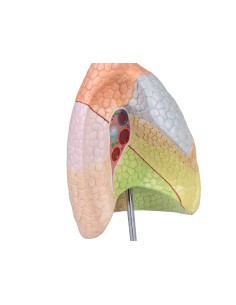

Modello per palpazione del seno, tre seni singoli su supporto - 3B Scientific L55

Modello per palpazione del seno, tre seni singoli su supporto - 3B Scientific L55